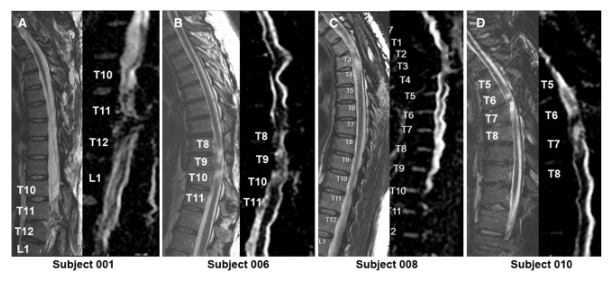

通過(guò) MRI 和 DTI 成像評估動(dòng)態(tài)反應

在 NSC 注射后,沒(méi)有放射學(xué)證據表明出現即時(shí)或延遲并發(fā)癥,包括術(shù)后即時(shí)或隨訪(fǎng)成像中沒(méi)有出現新的脊髓或軟組織水腫區域、增強或腫脹或積液。在純解剖或擴散張量序列中均未觀(guān)察到脊髓脊髓軟化癥的可見(jiàn)形態(tài)變化。

在所有四名患者中,彌散張量成像 (DTI) 成像顯示在損傷部位和損傷部位的前端/尾部脊髓束外觀(guān)穩定,但未顯示重塑或纖維束造影改善的廣泛證據。

MRI頸胸T2矢狀圖和AvDC矢狀圖